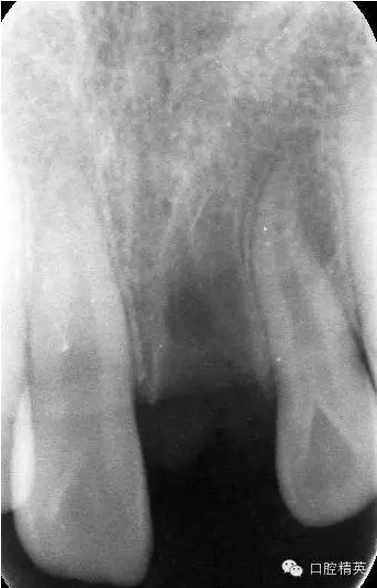

x線(xiàn)檢查:21牙槽窩空虛,窩內(nèi)未見(jiàn)其他遺留物。

圖3.患者21根尖片,牙槽窩空虛,無(wú)變形。